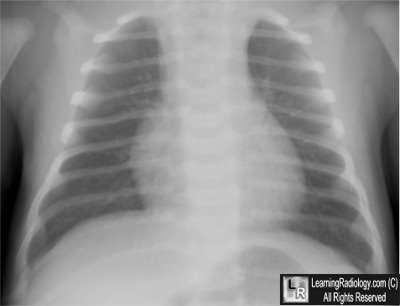

Additional Image-Chest x-ray done 3 days later

3 days after initial chest radiograph